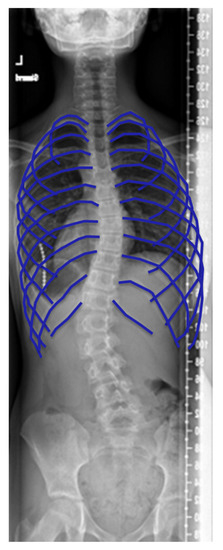

2.1. Radiography

- Apical vertebral body rib ratio and sternum rib ratio: An anterior–posterior radiograph is sufficient to measure the apical vertebral body rib ratio. From the apical body, the distance to the lateral borders of the ribs is measured in both directions [27]. While Kulko et al. describe it for an anterior–posterior radiograph, Mao et al. measure it on an axial reconstruction. Both parameters have been used to evaluate the pre- to postoperative shape of the thorax.

- Rib hump and chest wall angle: The rib hump and the chest wall angle are both an indicator of rib rotation. The chest wall angle is measured on the anterior part of the rib [24], whereas the rib hump is measured on the posterior parts of the ribs or sometimes also on Moiré topographs of the back [22]. Aaro et al. [25], Kuklo et al. [27] and Takahashi et al. [22] define the rib hump or the rib hump index slightly differently. However, the measured structures remain the same. On the posterior parts of the ribs, the distance in the anterior–posterior direction between the two prominences of the ribs is measured. This can be performed on a lateral radiograph [27] or on an axial CT scan [22]. The chest wall angle is a similar measurement but for the anterior rib prominences instead of the posterior rib prominence. In addition, instead of measuring a distance, the angle of the line connecting the prominences and the lateral plane is measured. Both the rib hump and the chest wall angle have significant correlations with the spinal curvature [22,24,25]. In addition, these parameters have been used for intraoperative comparisons of the thorax. It has been shown that the effect of surgery on the chest wall shape is very hard to predict [24].